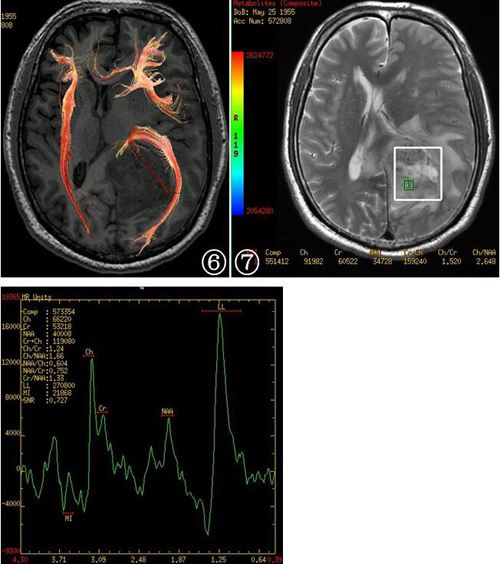

患者1月后常规返院复查,MRI示左侧颞顶枕叶-胼胝体压部左侧术区边缘呈环形强化,强化程度明显。胼胝体右侧新增一明显强化结节。考虑肿瘤复发可能,进一步行MRS检查,取胼胝体右侧新增病灶为感兴趣区示N-乙酰基天门冬氨酸(NAA)峰明显下降,胆碱(Cho)升高,综合考虑肿瘤复发。

图1~8患者术前头颅MRI检查。T1WI见左侧颞顶枕叶-胼胝体压部左侧占位,边界清楚肿瘤呈不均匀低信号(图1) T2WI呈不均匀稍高、高信号,其内见囊变区域(图2) 增强扫描病灶呈厚壁花环状明显强化,其内可见多发栅栏样条状强化(图3,4) DWI序列显示病灶呈高信号为主,其内间杂多发斑点状低信号(图5) DTI检查显示左侧额枕束中断(图6),MRS显示病灶内NAA峰明显下降,胆碱峰升高,并在1.33ppm处出现高耸的Lip峰(图7,8)